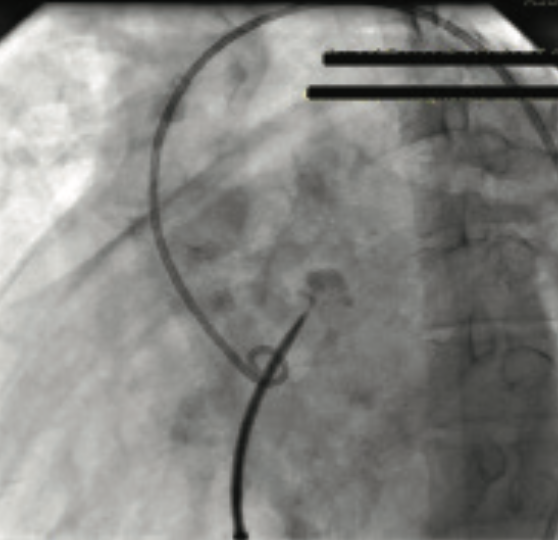

Percutaneous transvenous mitral commissurotomy (PTMC) has become the procedure of choice for the treatment of mitral stenosis (MS). This percutaneous treatment modality has a better safety profile when compared with surgery. The widely used Inoue technique employs a transvenous antegrade approach that initially requires a successful transseptal catheterization. Herein, we describe a case of aortic root puncture during a transseptal puncture using a Brockenbrough needle, leading an entire Mullins sheath dilator system into the aortic root. This potentially catastrophic complication, occurring in a 45-year-old female undergoing PTMC for severe MS, was effectively managed in a novel, percutaneous manner with the use of an Amplatzer Occluder device.